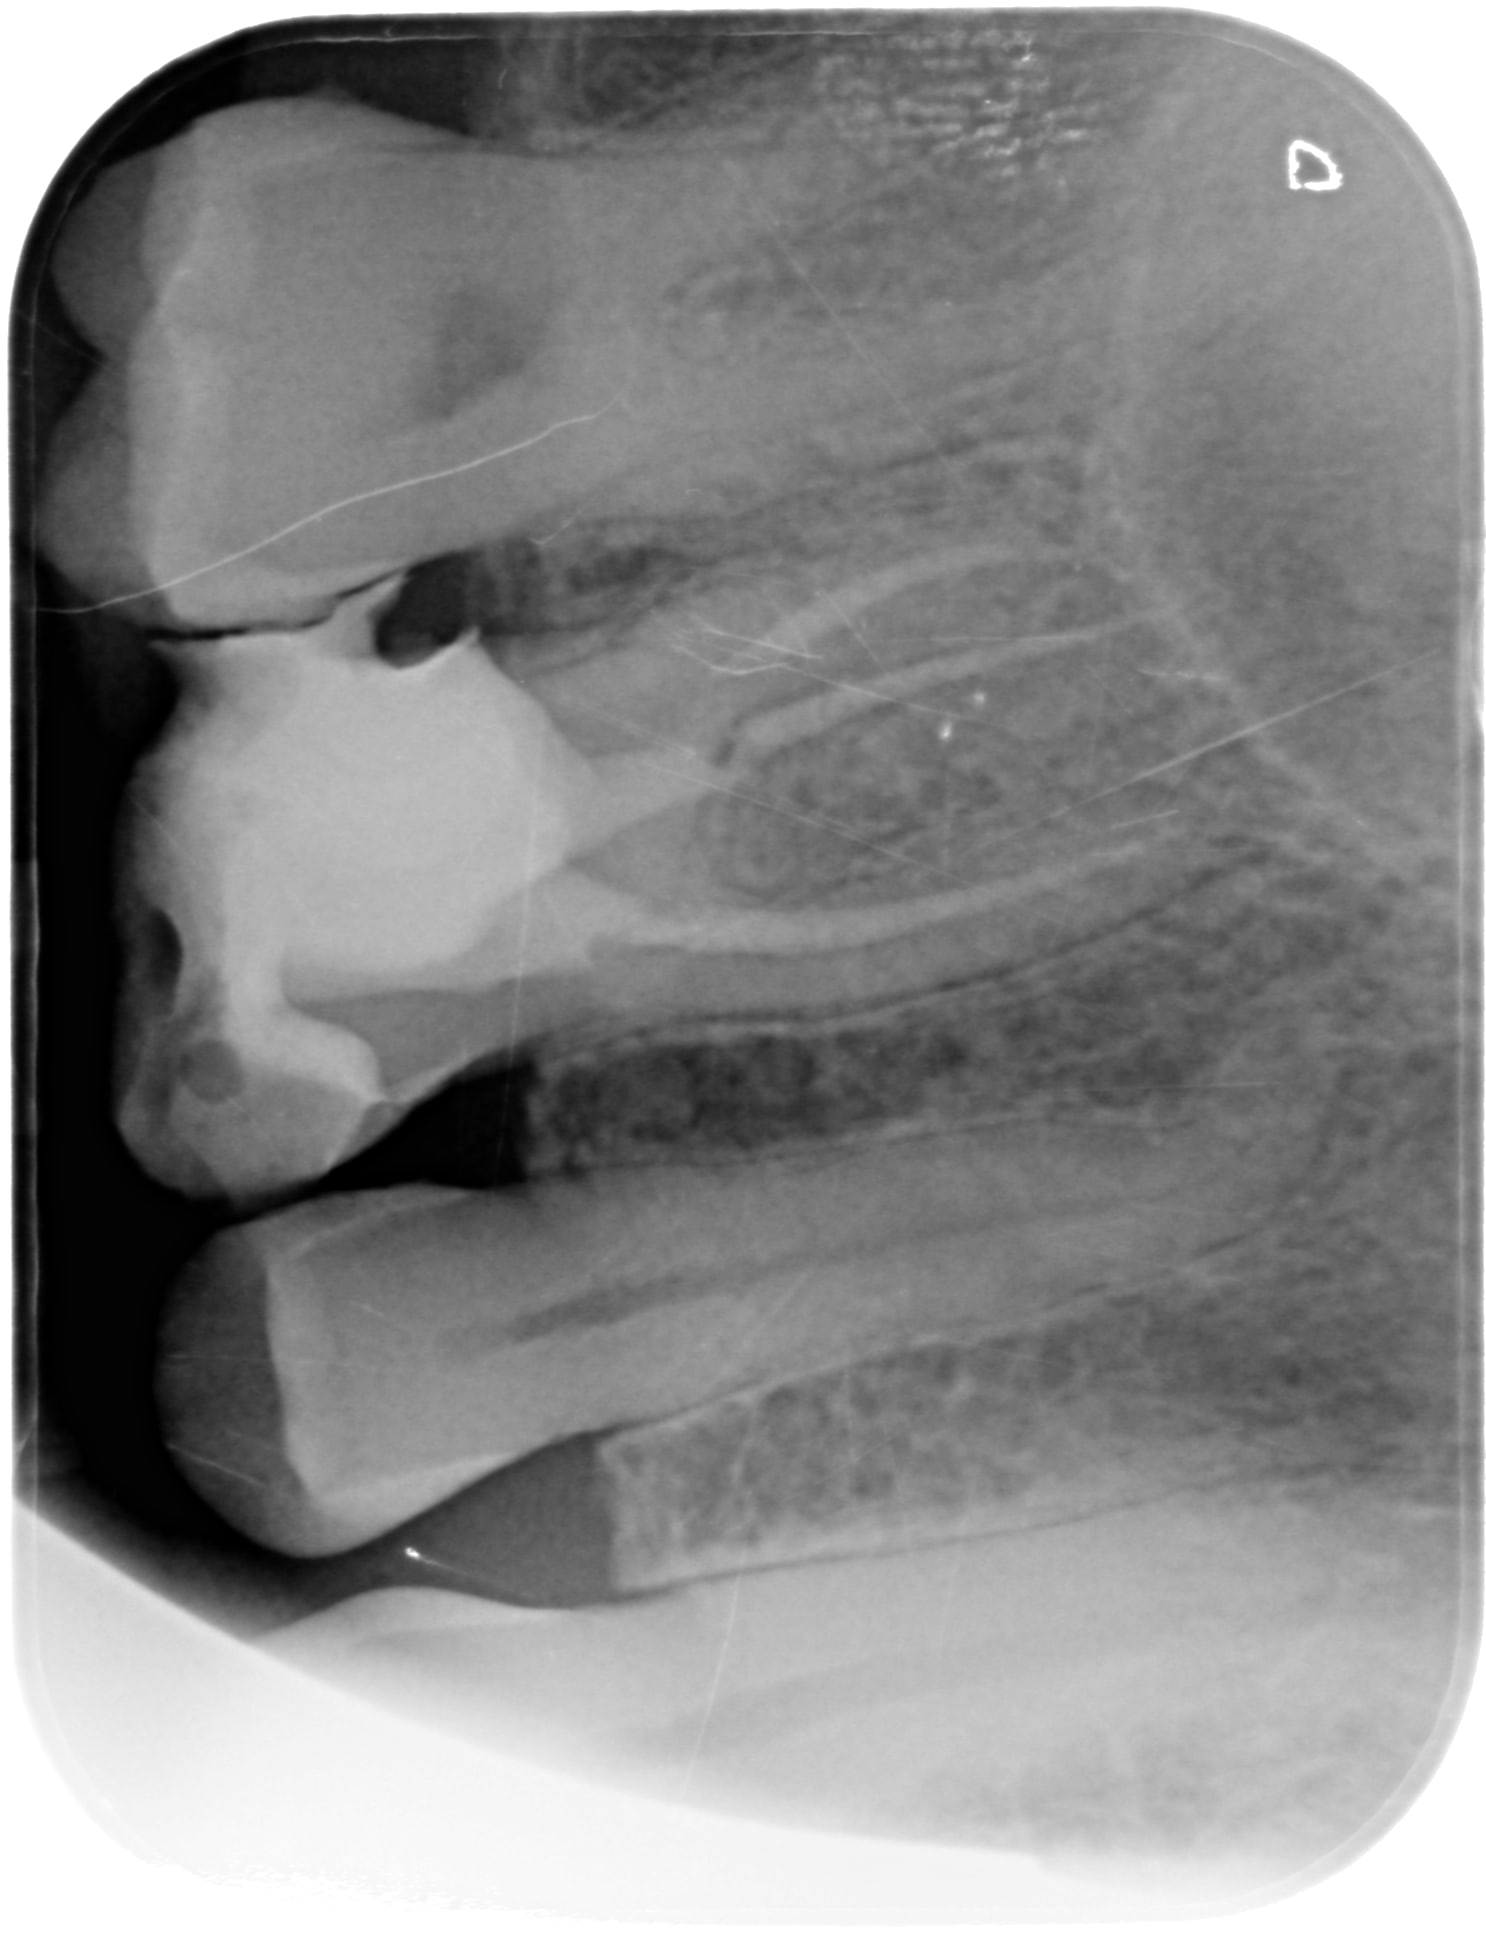

C'était le mv2 que je n'avais pas trouvé et qui s'était infecté.

Par contre, j espère que tu as une radio per OP crampon en place... Sinon c est une faute. Et la c est une autre histoire.

OP a mis la digue mais se disant que avec reciproc et localisateur d'apex il n'avait pas besoin de radio per op.